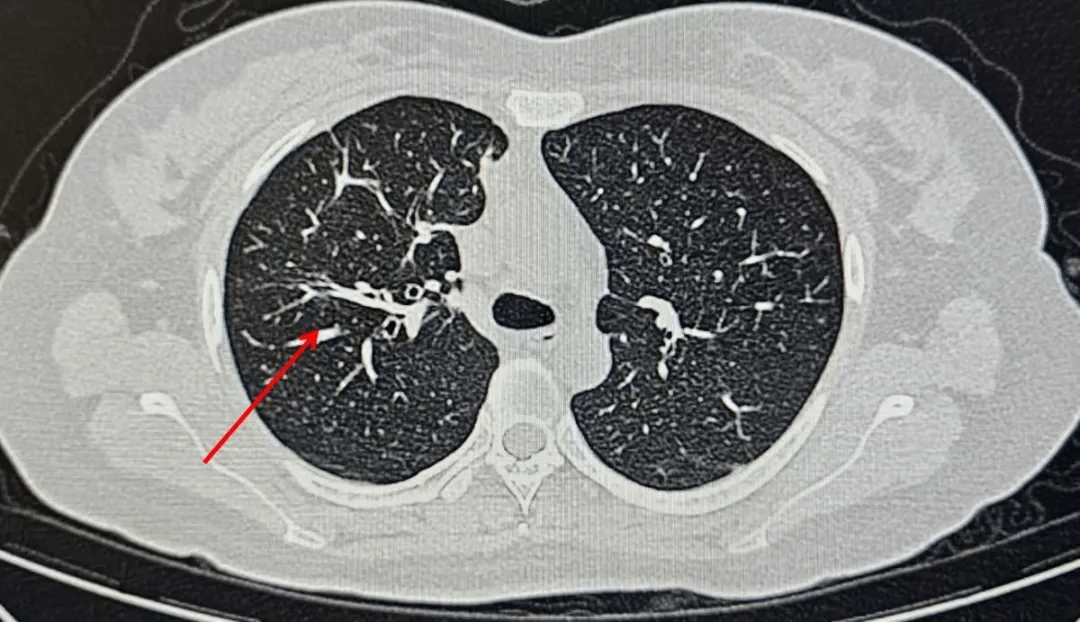

一周前,李女士因无明显诱因出现发热、咳嗽、咳痰,自行服药后症状不见好转,来到西安市第九医院呼吸与危重症医学科就诊。这一查不要紧,胸部CT显示:左肺上叶及中叶多发高密度影! 这样的影像学表现绝非普通感冒那么简单。

入院时胸部CT,左肺上叶及中叶多发高密度影

经过一段时间的规范抗真菌治疗,李女士的病情显著好转,复查胸部CT显示病灶明显吸收。目前李女士已出院,只需口服抗真菌药物并定期来门诊复查即可。